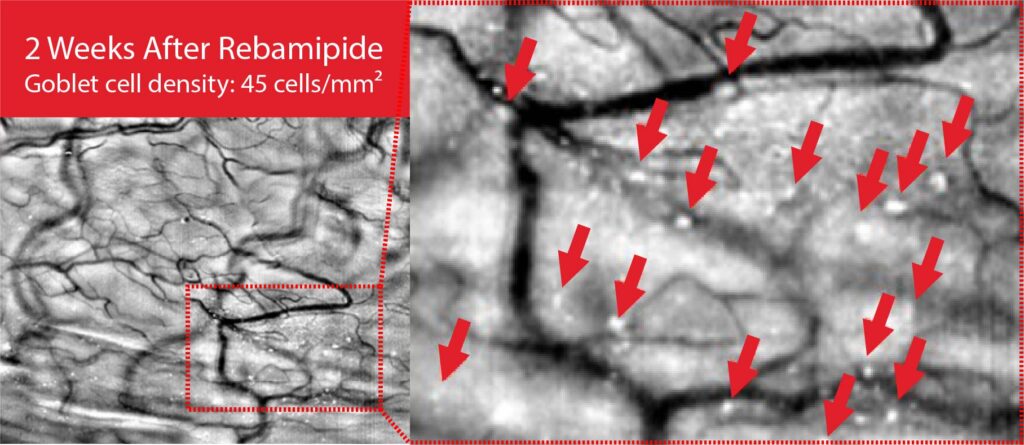

Goblet cells, located in the conjunctival epithelium, secrete the mucin MUC5AC to form the mucin layer of the tear film. They play a key role in maintaining tear film stability and lubricating the ocular surface. When goblet cells are damaged or reduced in number due to inflammation or external stimuli, mucin secretion declines, leading to tear film instability and the onset of ocular surface diseases such as dry eye.

Therefore, goblet cell analysis serves as an important diagnostic biomarker for evaluating the onset, severity, and treatment response of ocular surface disorders, including dry eye disease.

We have developed the world’s first imaging technology for conjunctival goblet cells, a core innovation that enables the diagnosis of various ocular diseases, including dry eye disease. Goblet cells serve as definitive biomarkers for dry eye and play a crucial role in maintaining immune tolerance. This breakthrough technology holds potential for expansion into diagnostics for other